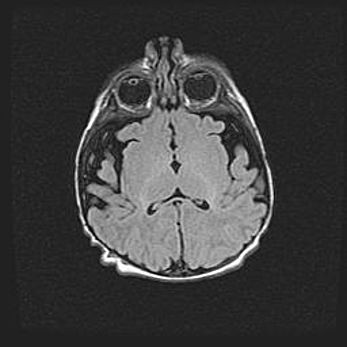

Церебральная ишемия II.

Возраст: 5 дней

Вес: 3400 г

Пол: женский

Окружность головы: 35 см

Срок гестации: 39 недель

Церебральная ишемия – это заболевание, характеризующееся недостаточностью (гипоксией) либо полным прекращением (аноксией) снабжения мозга кислородом по причине закупорки одного или нескольких сосудов. Это приводит к  что метаболическим расстройствам различной степени тяжести в тканях головного мозга, развитию коагуляционных некрозов и гибели нейронов.